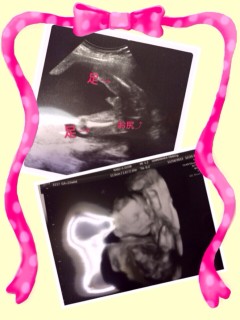

女の子でしょうとのこと! 絶対女の子だと思ってたので嬉しかったぁ 顔の形はパパ似かな? 足が立派すぎて、笑っちゃいました 赤ちゃん少し小さめみたいだけど 胎動が激しくて元気みたいです

男の子確定!伸ばしてる足の間に立派なものが写ってます♪

そして、そして、

堂々とシンボルを見せてくれました

先生に性別はどうしますか?と言われる前に分かってしまった(笑)

くっきり、はっきり!!男前さんでした。

旦那と母は女の子が良かったみたいだけど、私は男の子で嬉しいです(≧∇≦)